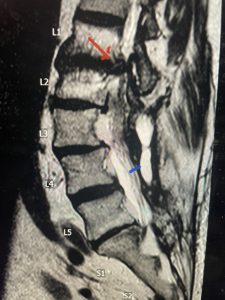

Epidural lipomatosis is a relatively rare condition where normally present fat in the epidural space is hypertrophied and can cause severe thecal sac compression. It is generally deposited more in the lateral and dorsal epidural space. This can be caused by long term steroid use and obesity, but also can be idiopathic. He had done well until more recently had developed low back pain with bilateral thigh pain and numbness. He had difficulty walking because of the pain. A new MRI (Fig 5) revealed that he had developed severe degeneration of the L1-2 segment above his prior decompression and fusion with a large extruded disc/osteophyte, right greater than left with severe thecal sac compression. He also had some residual T12-L3 residual epidural lipomatosis.

He had failed conservative treatment consisting of neurontin, physical therapy and epidural injections. He underwent revision laminectomy T12-L3 to decompress and explore prior fusion. He did have significant epidural fat encountered particularly at L1-2. The fat in epidural lipomatosis has a much more firm, globular texture. It takes a while to search within the fat, gently dissecting with a Penfield 4, to finally find the thecal sac! We encountered a large subligamentous extruded fragment lateral to the thecal sac on the right above the take off of the L2 nerve root. We removed any more residual fat at the L2-3 level and T12-L1 and decompressed the sac well. On exploration of the prior fusion it was fairly solid, but had some gaps at L2-3 fusion mass. Therefore we added a T12-L3 in situ fusion to augment those gaps and because we were at the thoracolumbar junction we extended fusion to T12. Post operatively he had relief of his leg pain.

(Figs 5a): Sagittal (a) and axial (b) T2-weighted lumbar MRI demonstrating status post lumbar decompression and insitu fusion L2-5 now well decompressed (blue dash) with development of new (red arrow) severe stenosis and with superimposed right L1-2 disc herniation (blue arrow)